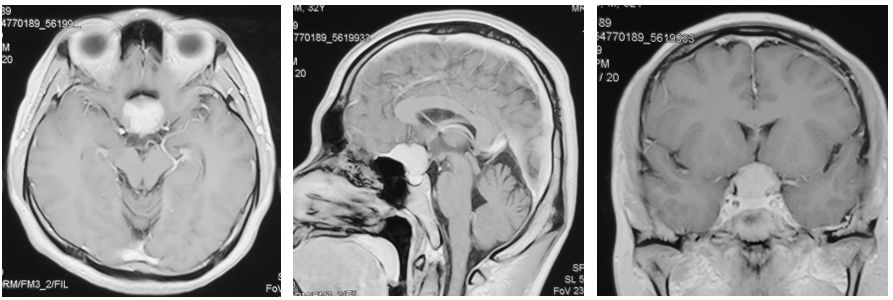

患者,男性,32岁;

主诉:视物模糊1个月;

体检: VOU 0.12,双眼颞侧偏盲,左眼甚。

- 术前诊断

鞍结节脑膜瘤

- 手术方案

左侧改良翼点开颅,内镜辅助肿瘤切除